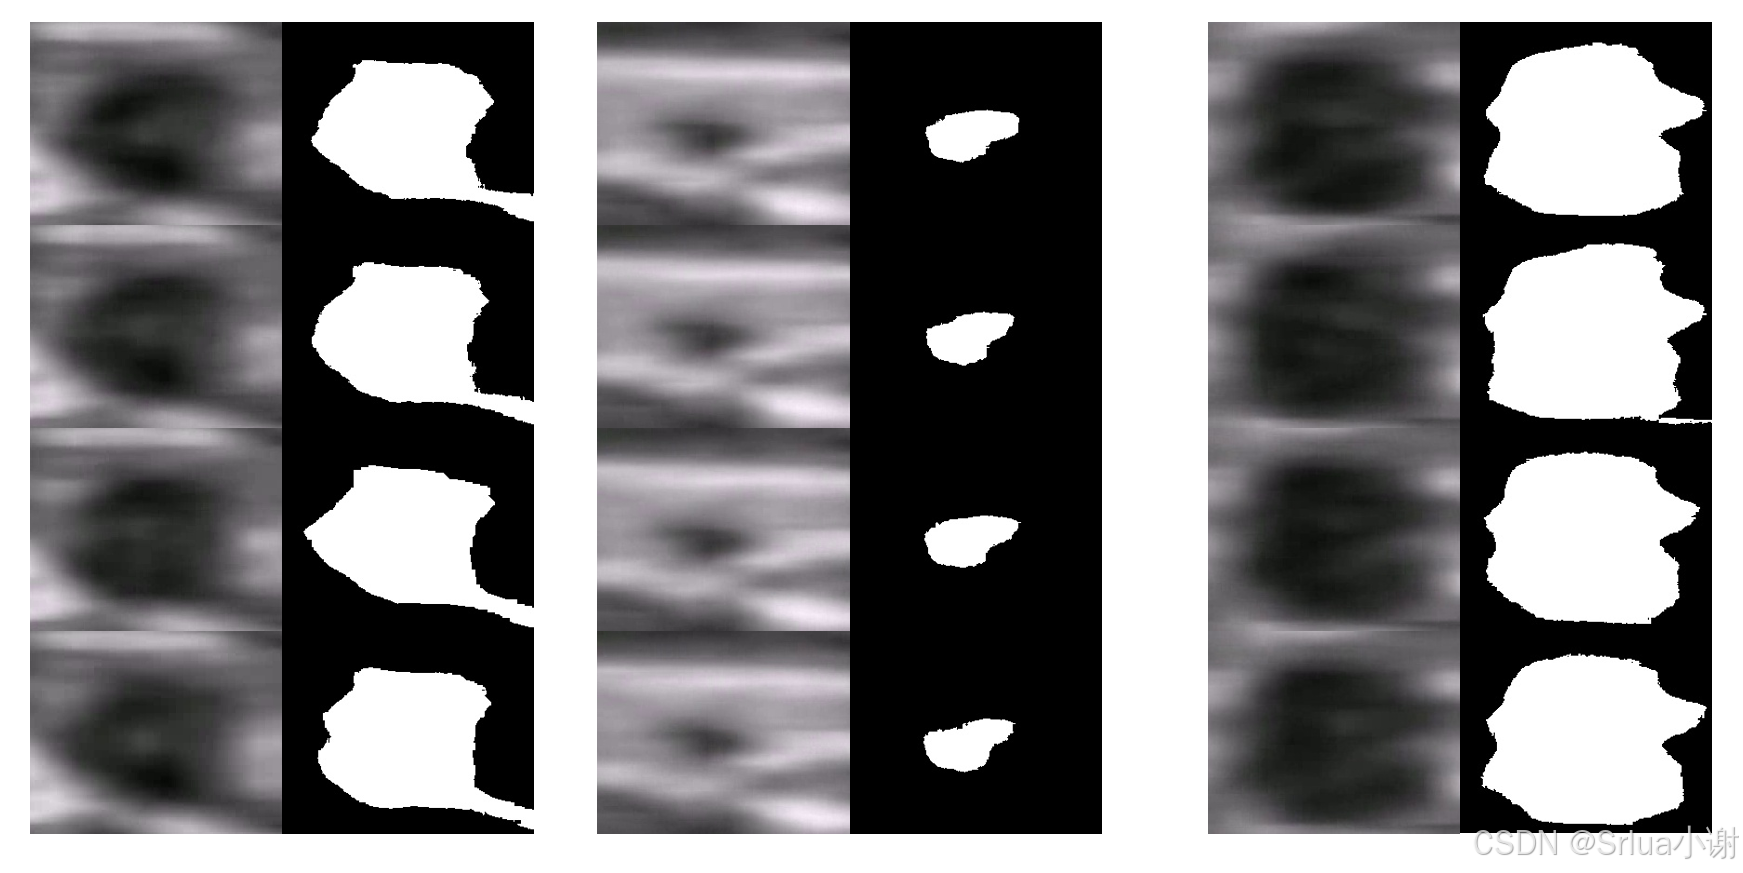

return thresh_img,pixel

可视化效果如下图所示,第一列为绑橡胶带前,第二列为绑橡胶带中,第三列为松橡胶带后。可以看出松绑之后明显要比帮之前要大,说明这个人血管弹性还是比较良好的。

但是这种算法有一个弊端,可以看出由于传统图像算法在进行分割时,往往会将红框中的非动脉区域错误分割,这也是不可避免的,所以我们提出了一种新的弹性分析算法。